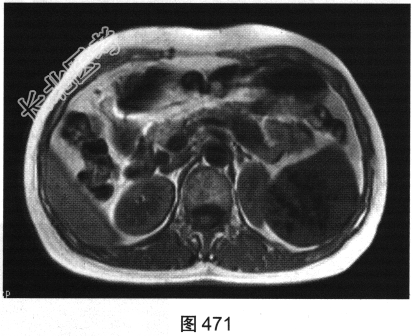

- 多项选择题4.[提示]为进一步明确诊断,患者行MRI检查, 如图470~图473所示。对MRI图像描述正确的是( )

A、T1WI呈不均匀稍低信号

B、左肾被病灶侵犯

C、病灶内见树枝状T1WI低信号、T2WI低信号影

D、门脉期可见造影剂进一步持续充填

E、动脉期轻度强化

F、抑脂T2WI呈不均匀稍高信号